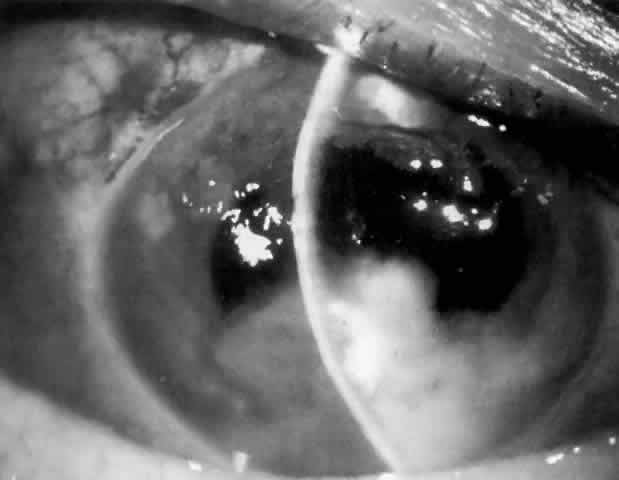

Cortical lens fragments retained in either the anterior chamber or the vitreous can also obstruct the trabecular meshwork in the form of free lens particles or macrophages swollen with lens material (Figs. 2 and 3). Glaucoma does not occur in all eyes that contain cortical remnants; the inflammatory response may be more pronounced and prolonged in eyes containing a higher amount of lens material. When inflammation is marked, keratic precipitates and sometimes a hypopyon may be present. Distinction between this sterile inflammatory endophthalmitis and infectious endophthalmitis can be difficult and may depend on the initial response to therapy. The presence or absence of IOP elevation is not helpful in making this distinction because IOP may be normal or elevated in both situations.

Fig. 2. Fluffy, hydrated cortical lens fragments retained in the anterior chamber after cataract extraction, resulting in inflammation and elevated intraocular pressure.